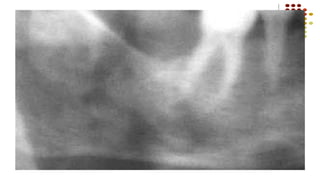

CONDENSING OSTEITIS-R/F

Localized area of increased radiodensity adjacent to the apex of the

tooth that exhibits a thickened periodontal ligament space

CHRONIC FOCAL SCLEROSING OSTEOMYELITIS

(CONDENSING OSTEITIS)

Localized areas of bone sclerosis in relation to the

apices of teeth with pulpitis or pulp necrosis

Unusual reaction of bone to infection occurring in

instances of extremely high tissue resistance or in

low grade infection